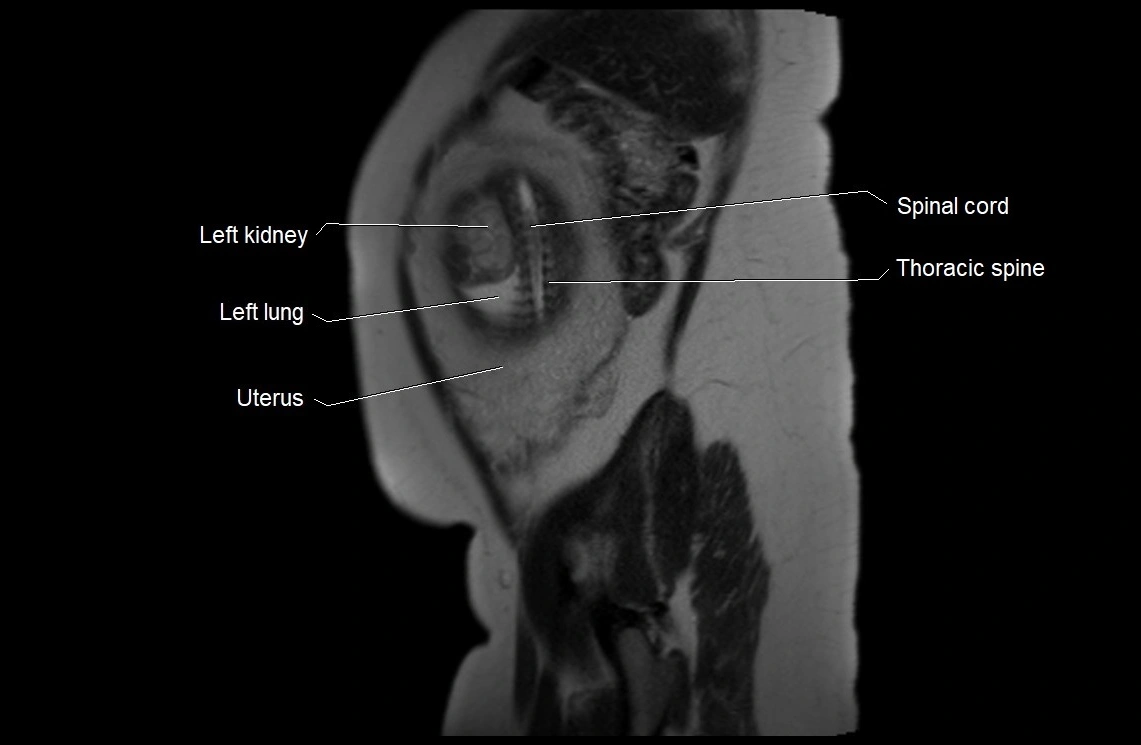

MRI Appearance

T2 HASTE (T2 GRE):

• Amniotic fluid shows very bright hyperintense signal

• Provides natural contrast against fetus and placenta

• Small particles (vernix) may appear as scattered hypointense foci within bright fluid

T1 GRE:

• Amniotic fluid shows low signal intensity (dark)

• Hemorrhage, infection, or proteinaceous content may cause focal or diffuse high signal intensity